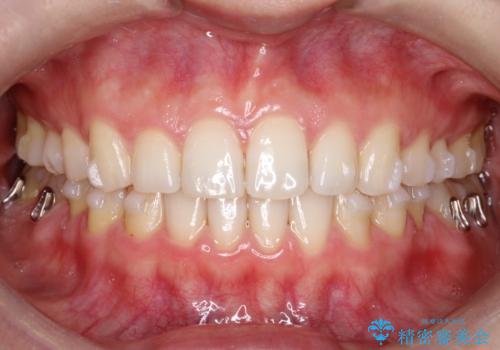

治療前は臼歯部反対咬合のため下顎が偏移し正中がずれていましたが、臼歯部反対咬合を改善したことで、正中のズレを改善することができました。